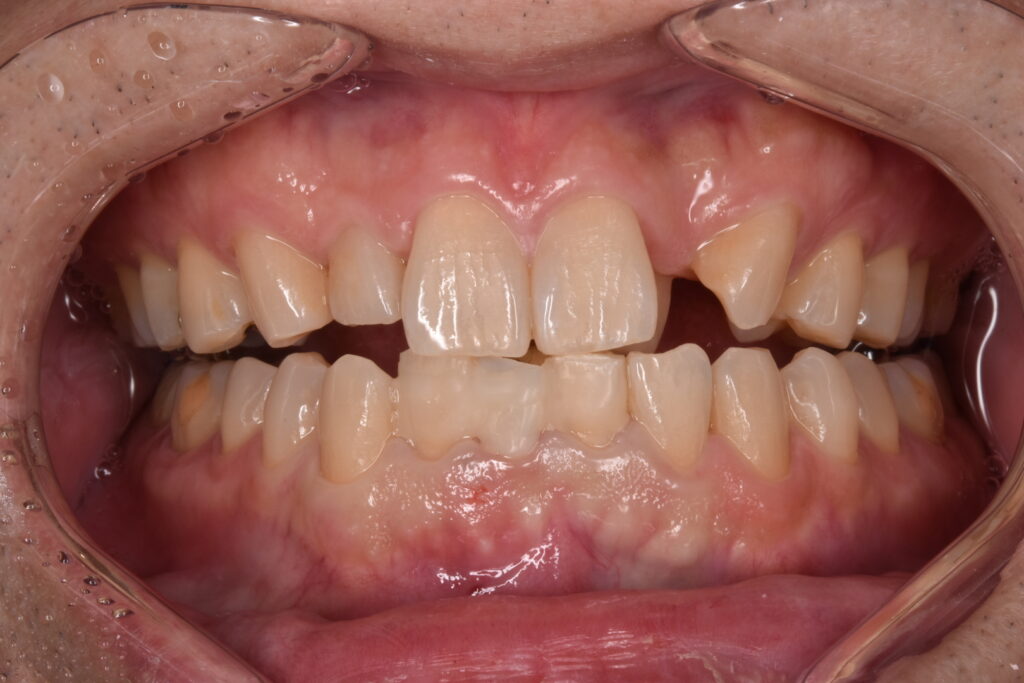

50代男性 下の前歯が東京の歯科で一年ほど前に作られた差し歯で、今回はそれが取れてしまったとご相談いただきました。検査の結果、歯が土台ごと折れていました。折れている場所が歯茎の中の方で折れていて、歯槽骨ギリギリの場所です。

さくらジルコニアプランでのジルコニアセラミックです。歯の色はA3というシェードです。色見本が20色近くありますので、そちらから選択して頂きます。